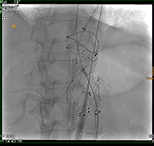

Nach Innsbruck kam Glodny aufgrund eines persönlichen Treffens mit o. Univ.-Prof. Dr. Werner Jaschke, dem Leiter der Innsbrucker Universitätsklinik für Radiologie. „Aus einem zunächst nur kurz angesetztem Termin bei ihm wurde ein mehrstündiges Gespräch, in dem ich erfahren habe, was hier in Innsbruck alles möglich ist und wie ich hier arbeiten kann“, erzählt Glodny rückblickend. Insbesondere die interventionelle Radiologie, durch die vielfältige therapeutische Eingriffe etwa in der Behandlung der arteriellen Verschlusskrankheit, oder von Blutungen oder Aneurysmen, von Tumoren- oder Metastasen möglich geworden sind, fasziniert den Radiologen und Forscher. „Mit durch Hochfrequenzstrom erzeugter Hitze, z. B. dem Verfahren der sogenannten Radiofrequenzablation, können Tumore oder Metastasen in Organen wie Leber, Niere oder Lunge behandelt werden. Die Vorteile dabei sind, dass ein oder mehrere Tumore extrem zielgenau und gründlich zerstört werden können, die ganze Prozedur aber für die Patient:innen sehr schonend ist. Die Absprache mit den behandelnden Kolleg:innen zur Erstellung eines individuellen interdisziplinären Behandlungskonzeptes für jede einzelne Patientin und jeden einzelnen Patienten garantiert die beste Versorgung.“ Am Standort Innsbruck schätzt Glodny vor allem das hohe fachliche Know How und gerät dabei nahezu ins Schwärmen: „Hier wird interventionelle Radiologie in absoluter Perfektion betrieben! Vor allem von Professor Reto Bale, der ein absoluter Experte auch in der Behandlung großer Tumore ist, kann ich sehr, sehr viel lernen. Darüber hinaus ist auch die Zusammenarbeit mit den Kolleg:innen aus der Universitätsklinik für Neuroradiologie unheimlich wertvoll und effektiv.“